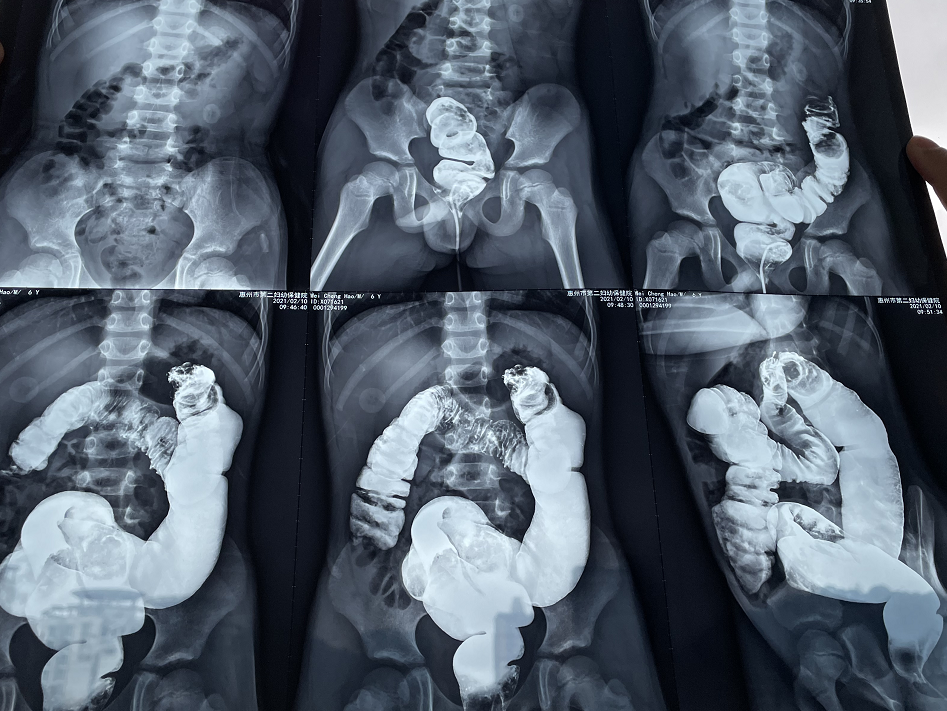

2021年2月,一位6歲幼童因腹痛在某醫(yī)院就診,經(jīng)腹部MRI檢查示:左中腹部實性腫塊,大小約3.6x3.6x2.8cm。鋇灌腸造影示結(jié)腸脾曲3x3cm類圓形低密度影,考慮結(jié)腸脾曲占位。

一切準備就緒,手術(shù)由內(nèi)鏡中心負責人徐永輝主任醫(yī)師、消化內(nèi)科劉華龍副主任醫(yī)師主刀。先進行了腸鏡檢查,進鏡至距離肛門約30cm處發(fā)現(xiàn)了這枚約3*4cm鵪鶉蛋大小的巨大息肉,已完全堵塞腸腔。